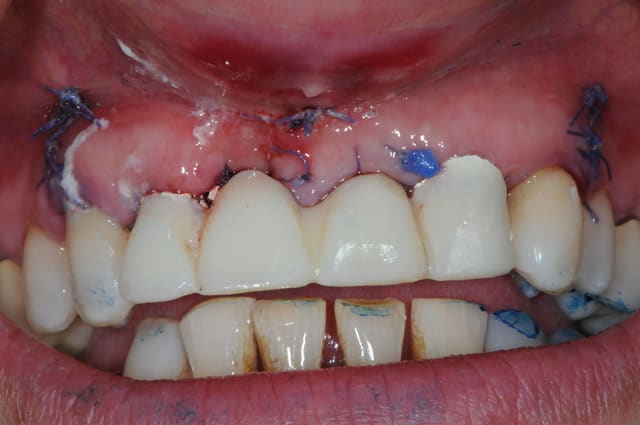

la ROG maintenant... ou "comment essayer de sauver les meubles"

photo 1: j+1 mois et demi

la cigarette à repris de plus bel, je suis désespéré mais bon, avec la chir muco gingival je devrais y arriver.

photo 2: j+3 mois